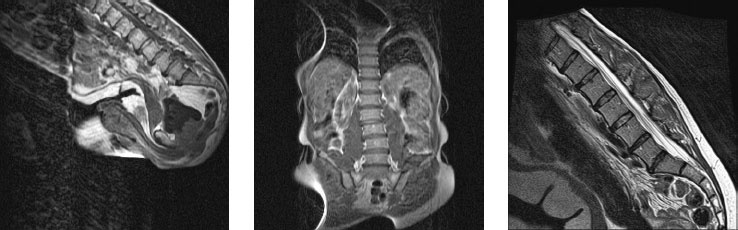

Специальные изменения в позах могут понадобиться людям с ампутированными конечностями, пациентам после инсульта и тем, у кого ограничены те или иные физические возможности. Например, при стенозе шейного отдела позвоночника не рекомендуется наклонять голову назад (изображение МРТ на рисунке 25 иллюстрирует возможный риск). Кроме того, обучая очень молодых людей, правильнее сосредоточиться на общей позе без дотошной корректировки деталей, поскольку она может быть воспринята как критика и лишит ученика всякого желания продолжать занятия. Для них гораздо полезнее выполнять упражнения с удовольствием, чем соблюдать все детали. В таких случаях компетентный учитель или терапевт станет ценным источником мудрости и безопасного обучения.

Иллюстрация к книге — Йога при остеопорозе [_28.jpg]

Рисунок 25. Запрокидывание головы значительно уменьшает диаметр и без того суженного позвоночного канала, приводя к спондилолистезу на уровне V шейного позвонка (удлиненный верхний позвонок – это II шейный). Сравните практически нормальный, слегка суженный канал в нейтральном положении (слева) и опасно сжатый спинномозговой канал при наклоне головы назад (справа). Опытные преподаватели с особой осторожностью следят за выполнением положений на сильную растяжку.